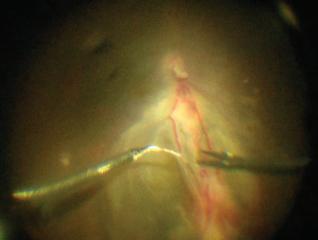

They turned to a complex and rarely performed intraocular surgical procedure in a final attempt to save the eye and prevent permanent and complete vision loss. Only recently described in medical literature, the groundbreaking surgery involved using microscopic instruments and ultrafine sutures to meticulously ligate the blood vessels feeding the tumor before carefully resecting the tumor itself.

Dr. Landa, a seasoned retina surgeon used to handling the most complex retinal, macula, and vitreous surgical cases referred to him from across the New York metropolitan area, was an integral part of that conversation. He mapped out a unique and bold surgical strategy with Dr. Patel for their young patient that could accomplish three critical goals within the same procedure: ligate the feeder blood vessels, resect the tumor, and attach the retina.

The two-hour surgery began with removing vitreous gel from the center and from the edges of the eyeball to access the fragile retina and the tumor’s dilated feeder vessels. Dr. Landa and Dr. Patel then moved on to the most challenging part of the surgery—isolating and ligating the two abnormal vessels. Using intraocular forceps and the finest available sutures, they gently

Fundus image of the tumor with a retinal detachment and the dilated feeder blood vessels

Ligation of the two abnormal vessels using intraocular forceps and sutures

tied off the vessels from within the eye to prevent potentially devastating bleeding.

“The vessels were unusually large and dilated,” says Dr. Patel. “We couldn’t simply use traditional cautery and cut them without causing severe bleeding. They had to be carefully tied off with sutures, all within the tight confines of the eye.” A bimanual surgical technique with micro forceps and ultrafine sutures allowed the surgeons to complete this challenging task.

With the feeder vessels sealed, the team proceeded to remove the tumor, which measured approximately 3 mm thick and 8 mm in diameter. The retina around the tumor was treated with additional diathermy to prevent bleeding, and both the tumor and surrounding retina were excised with minimal blood loss. The detached retina was repositioned and secured using laser

Surgical diagram showing key steps performed by Dr. Landa and Dr. Patel, including tumor removal, vessel ligation, and laser therapy to repair the retinal detachment

therapy, and a gas bubble was inserted into the eye to maintain retinal attachment during healing.